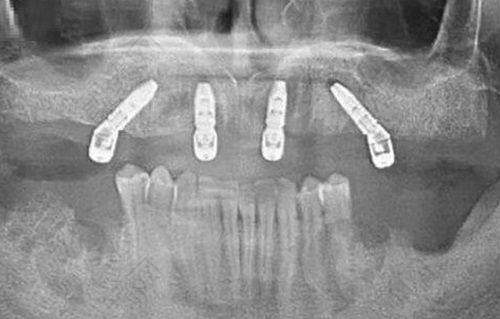

宁波鄞州德中口腔门诊部 - 牙齿种植 - 单颗种植体5000 - 15000元

患者评价一:在宁波鄞州德中口腔门诊部做了牙齿种植,体验非常好。从进门开始,工作人员就热情接待,引导我完成各项检查。医生特别专精,详细地给我讲解了种植方案和注意事项。种植过程中没有感觉到明显的疼痛,术后修复也特别快。现在牙齿使用起来特别正常,非常感谢德中口腔。